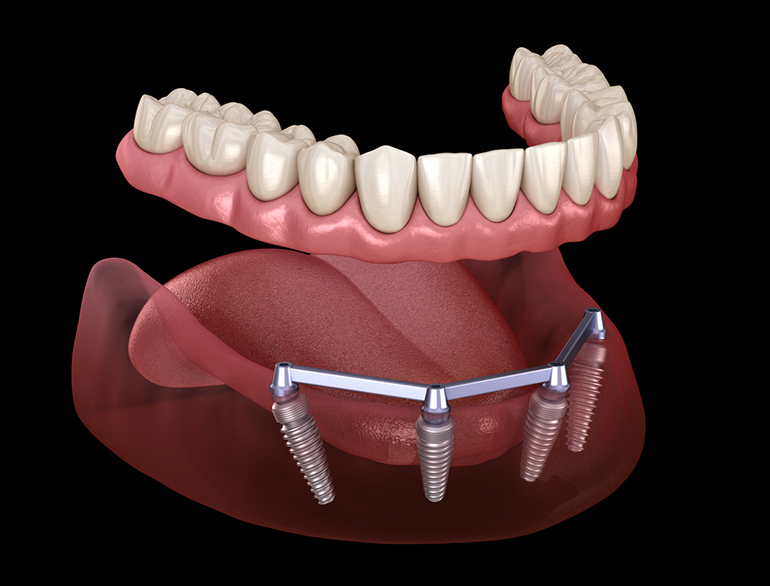

Modern dentistry has developed 3 types of dental implants, best known for their long endurance, high success rate and overall reliability.

Depending on your circumstances, one type might be better than the other. The decision is yours, but we advise you to pay careful attention to your dentist’s recommendations: